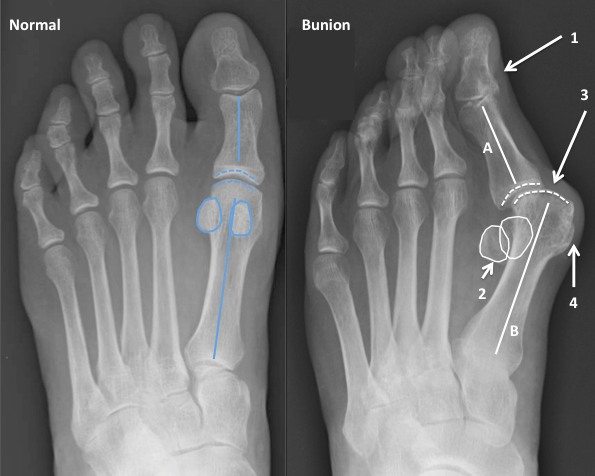

Медицинские решения: Операция по коррекции Hallux valgus